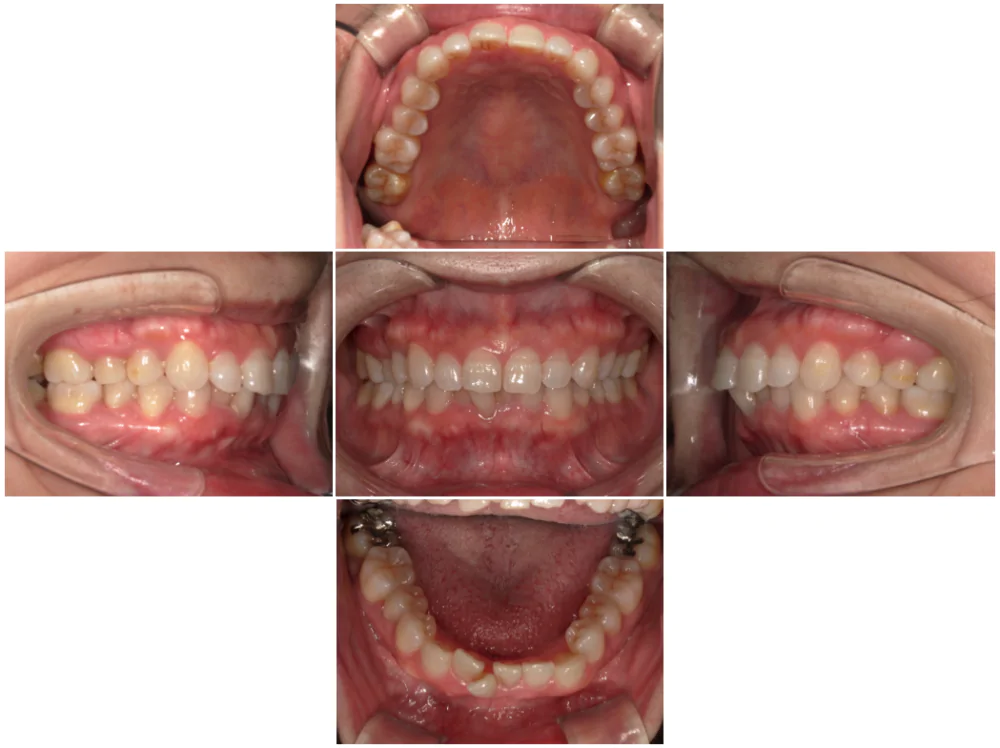

症例2

| 来院時の主訴 | 前歯がガタガタ |

| 医院での対応や適用装置 | マウスピース矯正装置を使用して主訴である叢生の改善を行ないま |

| 通院期間 | 1年3ヶ月 |

| 通院回数 | 9回 |

| 治療費用総額 | 819,500円(税込) |

| リスクと副作用 | 矯正治療による歯の移動に伴う痛み、歯根吸収、虫歯 |